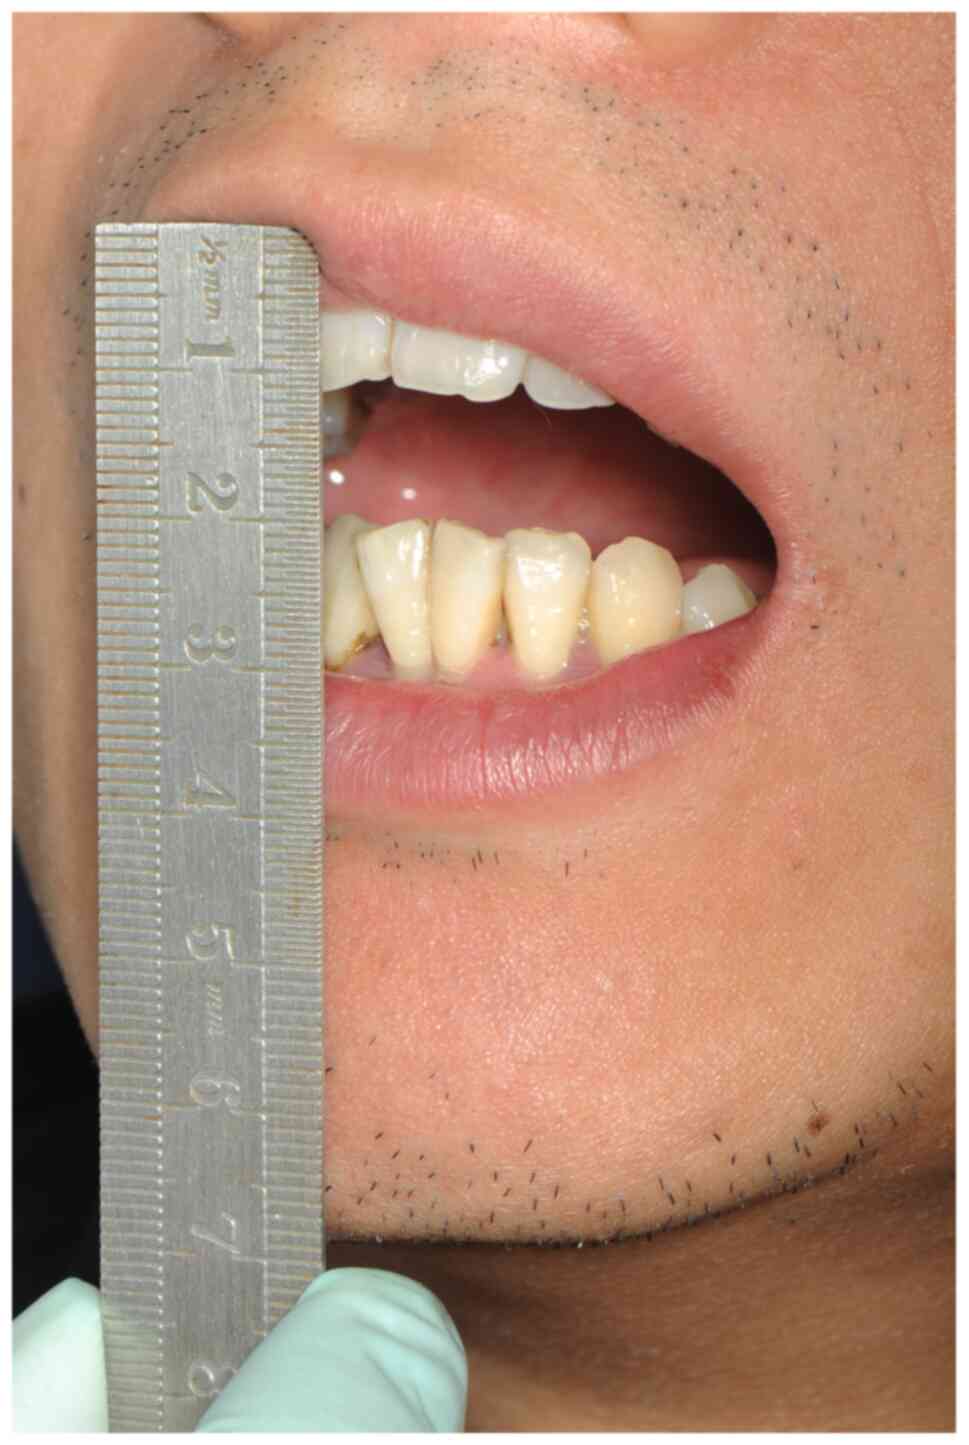

Persistent trismus following mandibular third molar extraction and its management: A case report and literature review

Trismus is one of the common complications which occur following the extraction of mandibular impacted third molars. This generally occurs due to low‑grade infection, repeated muscle stimulation, as well as other causes. This symptom is usually relieved after 1 to 2 weeks; however, it may persist for >1 month post‑operatively in very rare cases. The present study reports the case of a patient with trismus at 45 days following mandibular third molar extraction. The patient received local and systemic anti‑inflammatory treatment, combined with incision and drainage therapy under local anesthesia. In the present study, an analysis of the factors associated with the occurrence and development of trismus is also included, as well as appropriate management strategies in order to provide an effective treatment method for affected patients and for the prevention of trismus in the future.

Figure 1

Figure 2

Figure 3

Figure 4

Figure 5